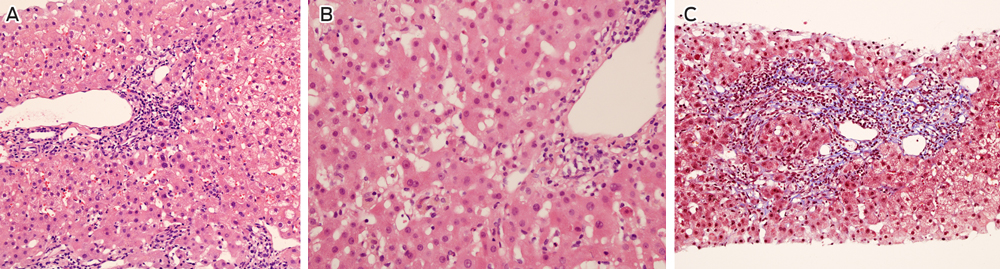

The patient adhered to his immunosuppressive regimen and had not commenced other medications. Physical examination was unremarkable and abdominal ultrasound did not show biliary or hepatic vascular abnormalities. A liver biopsy was performed and reported as consistent with moderately active acute rejection. This prompted methylprednisolone therapy (500 mg once daily for 3 days) followed by prednisolone (50 mg once daily) and replacement of cyclosporin with tacrolimus (3 mg twice daily). MMF was continued unchanged. A second liver biopsy was performed 1 week later due to a further rise in the ALT level (456 U/L), which demonstrated non-specific hepatitis without definite features of rejection or an autoimmune aetiology (Box 2). Subsequent comparison of these biopsies by a specialist histopathologist confirmed acute hepatitis in both samples, without significant features of rejection on either biopsy.